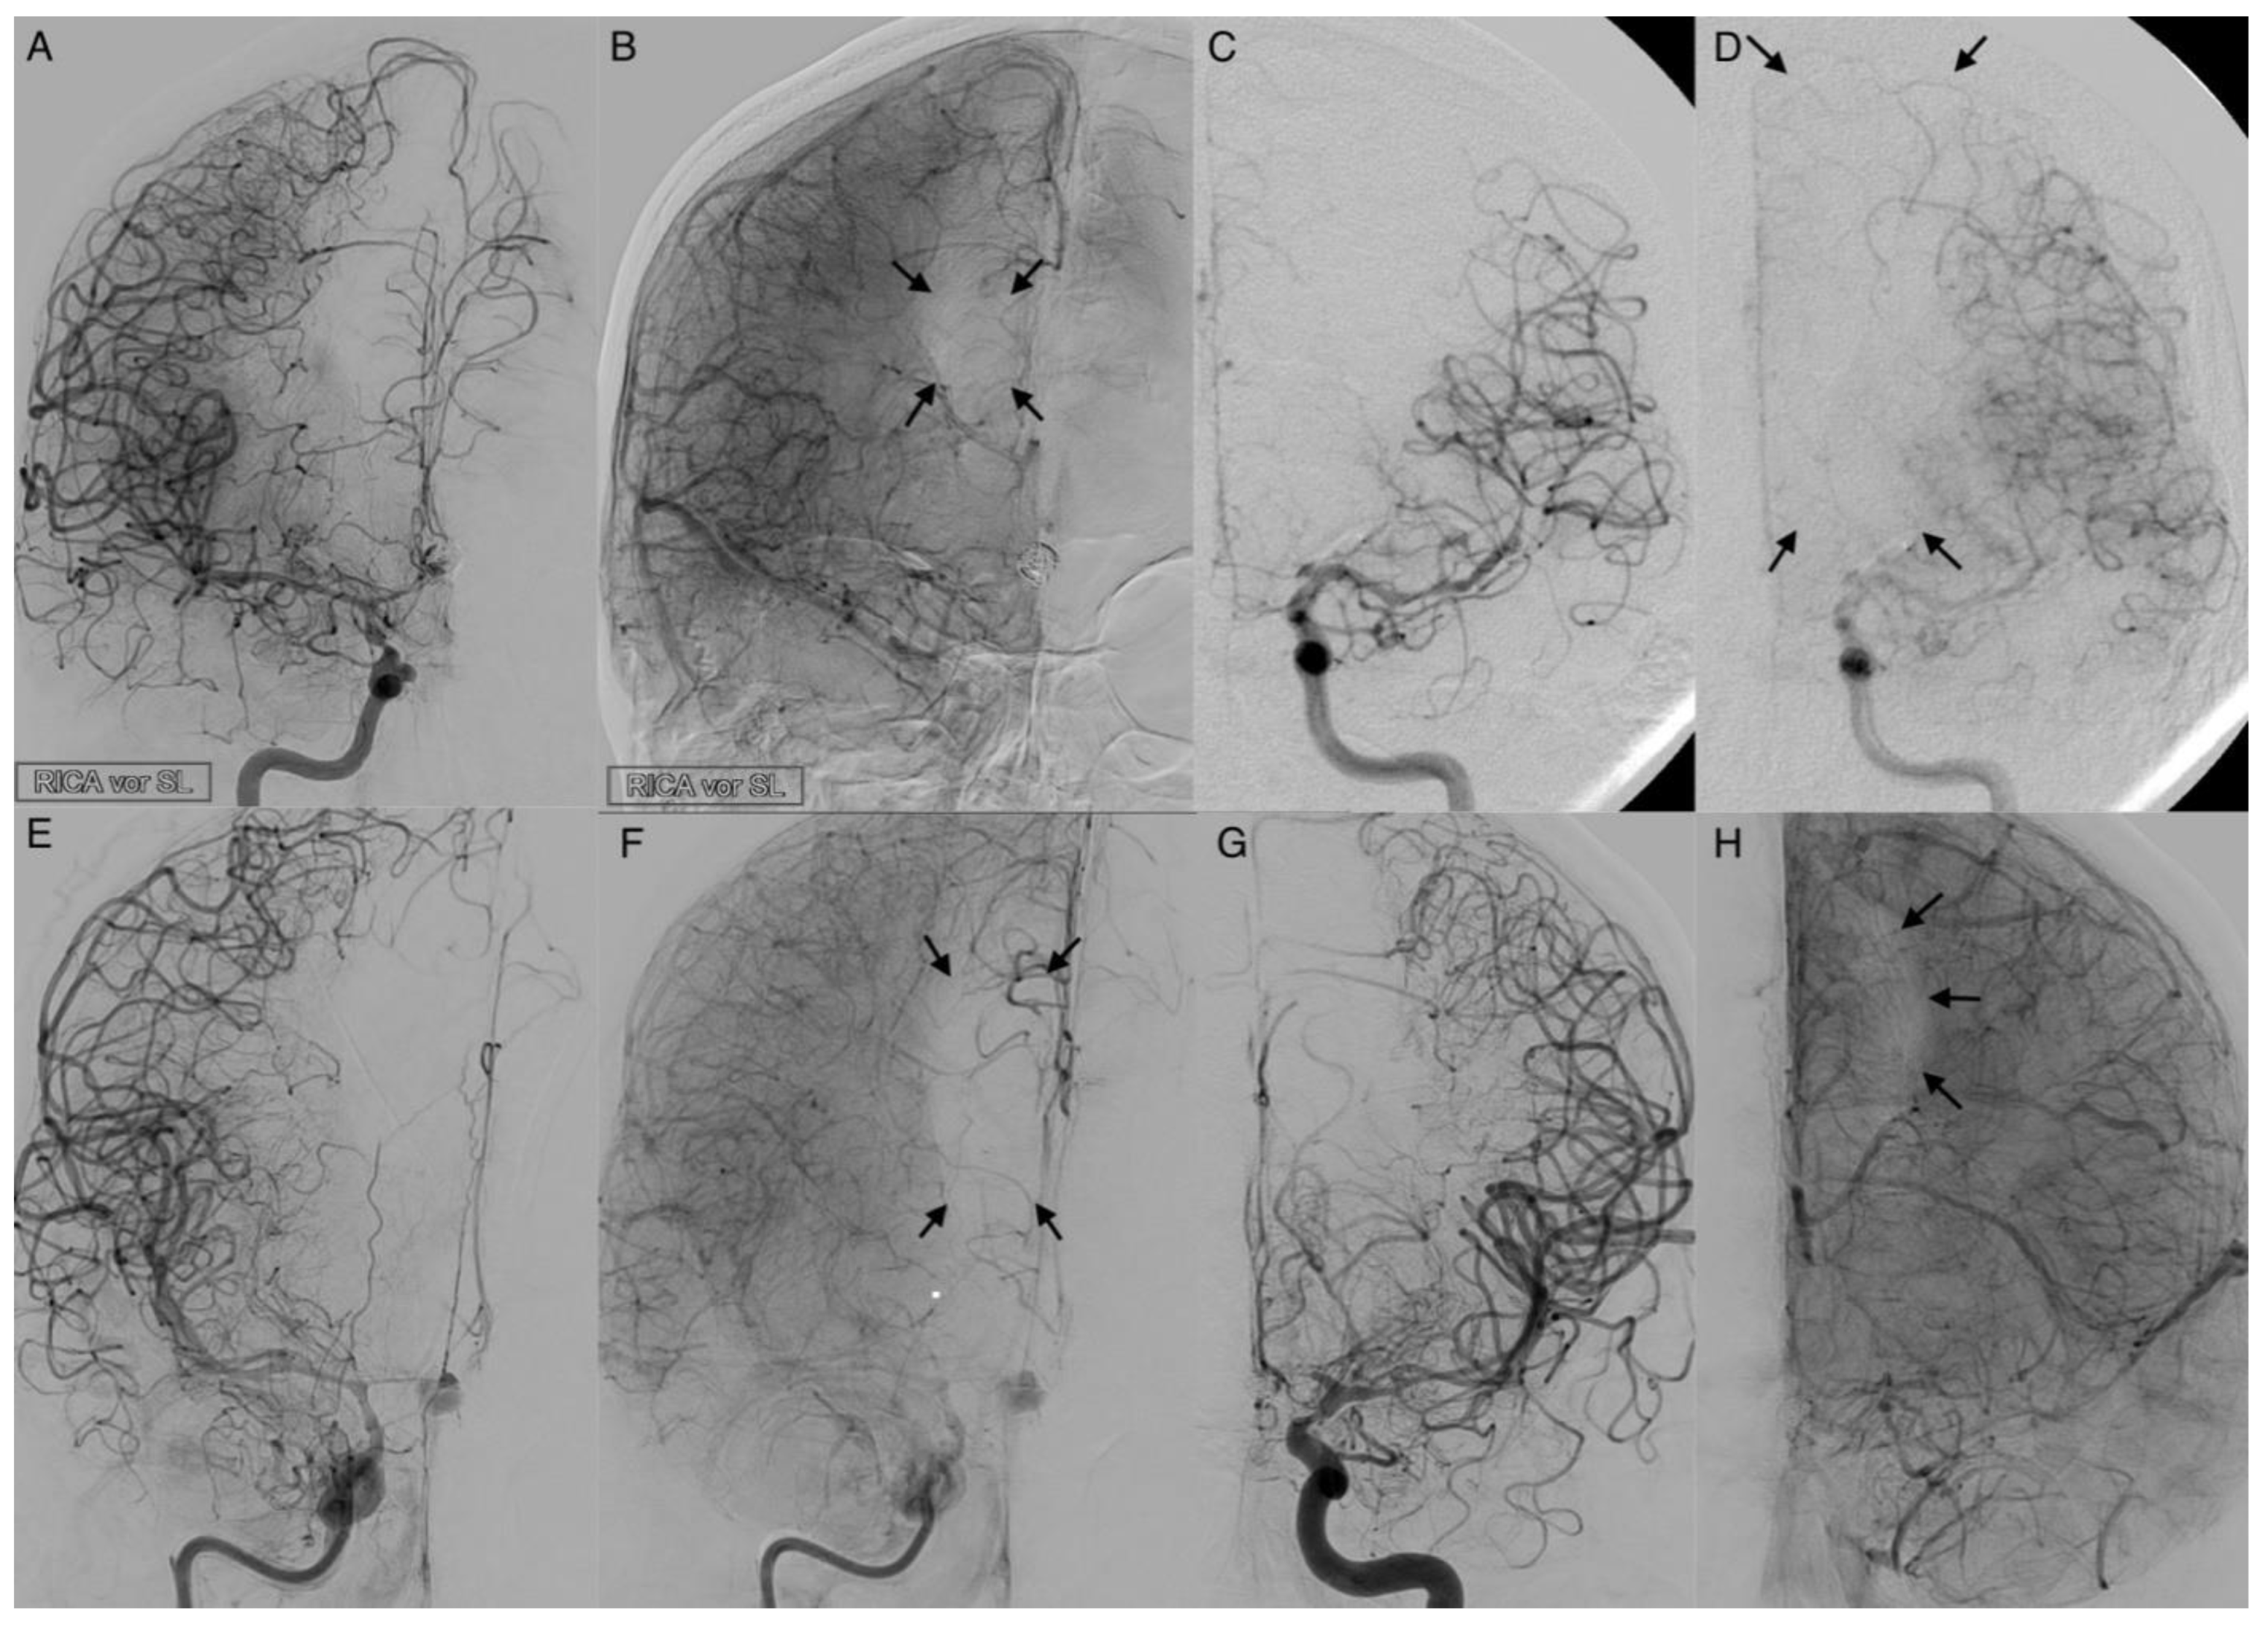

3.4. Leptomeningeal Collaterals

The activation of leptomeningeal collaterals between the MCA and ACA territory was assessed in p.a. projection. The varying ability of collateral supply is shown in Figure 5 and Figure 6. Two patients first had activated collateral supply, but later had collapsed collateral supply (Figure 6). The distinct outcomes with mRS values of 3 and 5, despite subtotal hemispheric infarction, were caused by the laterality of language ability.

In all cases with collateral supply, vasospasm had affected the ACA hardest, requiring leptomeningeal collaterals to take over the anterior and border zone supply. Only 37.2% (n = 16) of patients revealed a leptomeningeal collateral activation on angiograms (Table 1). Fourteen patients (87.5%) with leptomeningeal collateral activation showed a positive STA sign on angiograms with a positive correlation in Pearson’s correlation (Correlation coefficient: 0.318, p = 0.038). Overall, Fisher’s test indicated no significance for the prediction of outcome (p = 1) or DCI (p = 0.719) in the context of leptomeningeal activation.

Figure 5. Activated leptomeningeal collaterals in anterior cerebral artery vasospasm. The angiograms show the extent of collateralization in four cases of severe cerebral vasospasm following aneurysmal subarachnoid hemorrhage. The arterial phase (A,C,E,G) reveals a strongly narrowed and decelerated anterior cerebral artery. In the parenchymal phase (B,D,F,H), activated leptomeningeal collaterals of the middle cerebral artery took over the retrograde supply of the decelerated parenchyma with varying extent of the remaining perfusion defect (arrows).